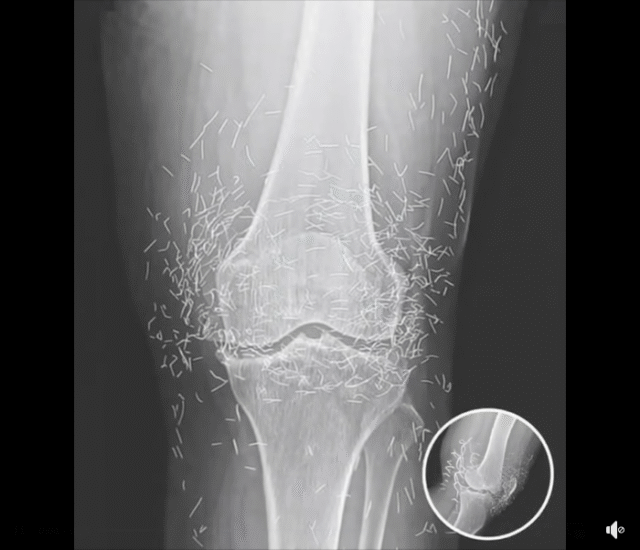

What started as a routine hospital visit for knee pain turned into a medical mystery that left doctors speechless. A 65-year-old woman in South Korea went in expecting a diagnosis of arthritis — but when her X-ray appeared on the screen, the room fell silent. Her knee joint wasn’t just worn down from age; it was filled with dozens of tiny gold needles. The strange discovery sparked immediate questions about how they got there and why they had remained unnoticed for so long.

The shocking X-ray served as a cautionary reminder of how alternative treatments can sometimes go too far. Specialists warn that leaving any metal object inside the body can cause inflammation, infection, and complications during imaging procedures. While acupuncture, when performed properly, is generally considered safe, experts emphasize that permanent implants are not medically approved or supported by evidence.